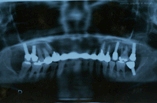

◎初診時の状態 ・上の左右1歯ずつ、ぐらついて噛めない ・歯ぐきが痛んで出血する ・奥歯でしっかり噛むことが出来ない ◎患者様の希望 ・インプラントをしてもらいたい |

| 【治療内容】 ぐらついていた2本の歯を抜歯し、全体の歯周治療を行い、歯ぐきの改善を図りました。 奥歯でしっかり噛めるように失われた5ヶ所にインプラントを入れ、最後に見た目がキレイにとの希望がございましたので、セラミック・クラウン(白い冠)を装着しました。 |